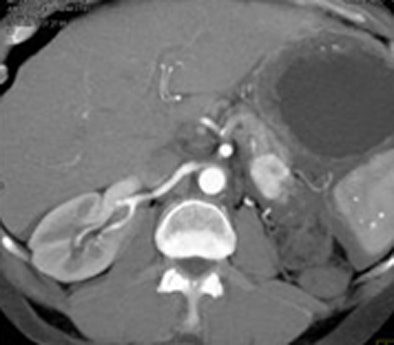

![]() |

| A splenic artery aneurysm mimics an islet cell tumor. |

"It's very easy to make mistakes, particularly by the head of the pancreas and the tail of the pancreas," he said. For example, a splenic artery aneurysm can easily be misdiagnosed as an islet cell tumor or a splenule, he said.

"Splenic lesions very much at times simulate pancreatic masses; it's a very difficult area," Fishman said. You have to look at arterial and venous phase enhancement, he said. One clue is that enhancement of the splenic artery is significantly matched with that of the spleen.

Findings involving the splenic artery, particularly if the artery is very tortuous, can easily simulate distal pancreatic lesions, Fishman said.